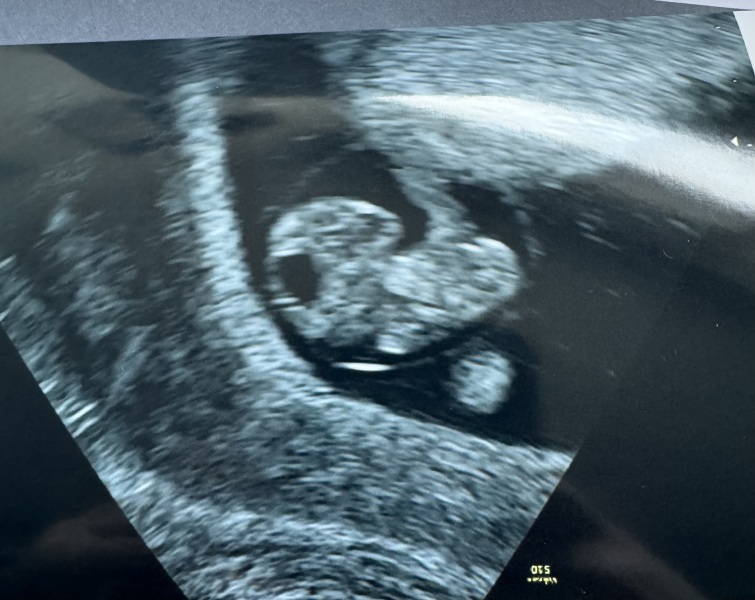

VT6 · 03/02/2024 15:17

I cried at my scan, seeing the little heartbeat makes it all very real!

Bang on 8weeks so got my dates perfect!

Maybe I can relax now 🤣

@VT6 great scan pic, hopefully it all feels real now and you can relax a little xx